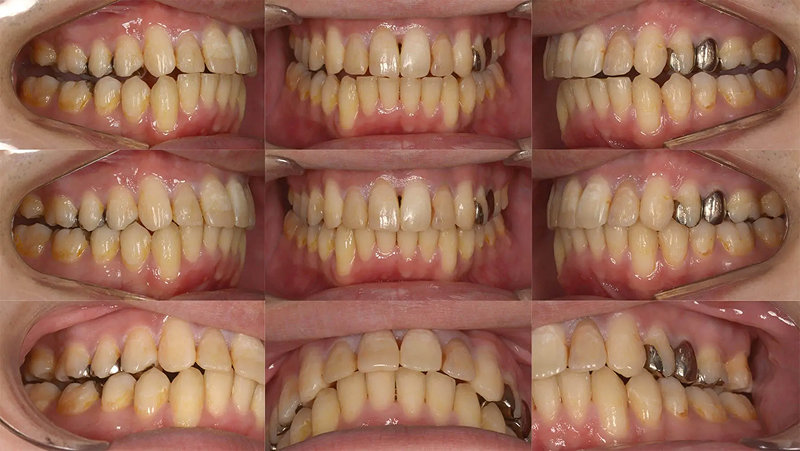

Case01全体的な凸凹を改善した症例

大学4年生の5月に来院して、卒業までに矯正治療が終わるかということでした。就職すると歯科医院に通院するのが難しいからと強い希望を持っていました。診査の結果、歯列の拡大で行えギリギリ間に合う診断をしました。矯正治療後、審美治療を行う時間もあり、十分、納得のいく治療をすることができました。

口元比較

Before

After

初診 2017.5.24

矯正治療開始 2017.6.19

矯正治療終了(9か月) 2018.3.6

ファイナル 2018.3.16

| 主訴 | 全体的な凸凹を治したい |

|---|---|

| 診断 | 両側アングル1級の叢生 |

| 矯正方法 | オーバーレイアーチを用いたマルチブラケット |

| 矯正期間 | 9か月・10回 |

| 費用 | 750,000円(税別) |

| 調整料 | 月1回 5,000円(税別) |